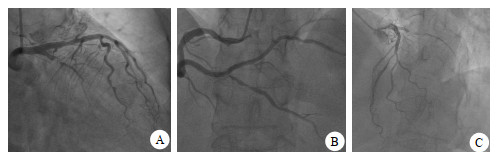

1 资料与方法病例1,男,63岁。持续性胸背部不适伴胸闷气促6 h于2021年12月5日急诊以AMI入院,心电图提示下壁Q波形成(图 1)。肌钙蛋白(cardiac troponin, cTnI)7.10 ng/mL,肌酸激酶同工酶(creatine kinase isoenzyme, CK-MB)22.5 ng/mL(图 2)。急诊经皮冠状动脉介入治疗(percutaneous coronary intervention, PCI):右冠脉左室后支(posterior branches of left ventricular, PL)100%(图 3A),为罪犯血管,右冠脉后降支(posterior descending artery, PDA)75%狭窄(图 3B),左前降支(left anterior descending artery, LAD)80%狭窄。开通罪犯血管PL,球囊扩张后置入2.5 mm×31.0 mm支架,患者胸闷气短症状缓解。考虑到罪犯血管放支架后血流动力学尚稳定,非罪犯血管是否缺血,是否需要干预治疗,决定行非罪犯血管FFR测定。测定结果PDA 0.76,LAD 0.69均需干预治疗,行OCT检查观察狭窄处冠脉钙化及纤维化的严重程度来决定是急诊干预还是择期干预。检查结果示PDA冠脉内轻度纤维化,决定急诊干预,置入2.5 mm×31.0 mm支架,再行FFR测定为0.88(阴性),而LAD的FFR为0.69(阳性),OCT检查冠脉内严重环状钙化伴重度纤维化并脂质斑块形成(图 3C),而且病变较长,急诊干预有引起冠脉夹层弊病的可能,为安全改为择期处理。

| A为PL 100%;B为开通PL、PDA后FFR 0.76,支架植入后FFR 0.88;C为LAD,OCT冠脉内严重环状钙化 图 3 病例1的冠脉造影及OCT检查结果 |